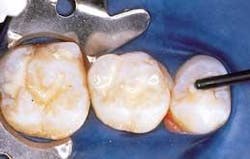

• After the area is isolated, I first prepare the surface by conditioning the site with Ecusit® Etch (Figure 3) for 15 to 30 seconds, covering all surfaces in one continuous motion. The Ecusit etching gel is a water-based, 37 percent phosphoric acid gel. The gel is blue for easy identification against the tooth structure. Then rinse with water spray and dry. The enamel should have a "frosted" appearance (Figure 4).

• Next is the placement of the EcuSeal (Figure 5). I start at the most distal end of the most distal tooth to be sealed in the quadrant, moving the Ecu-PEN in a continuous motion toward the mesial.